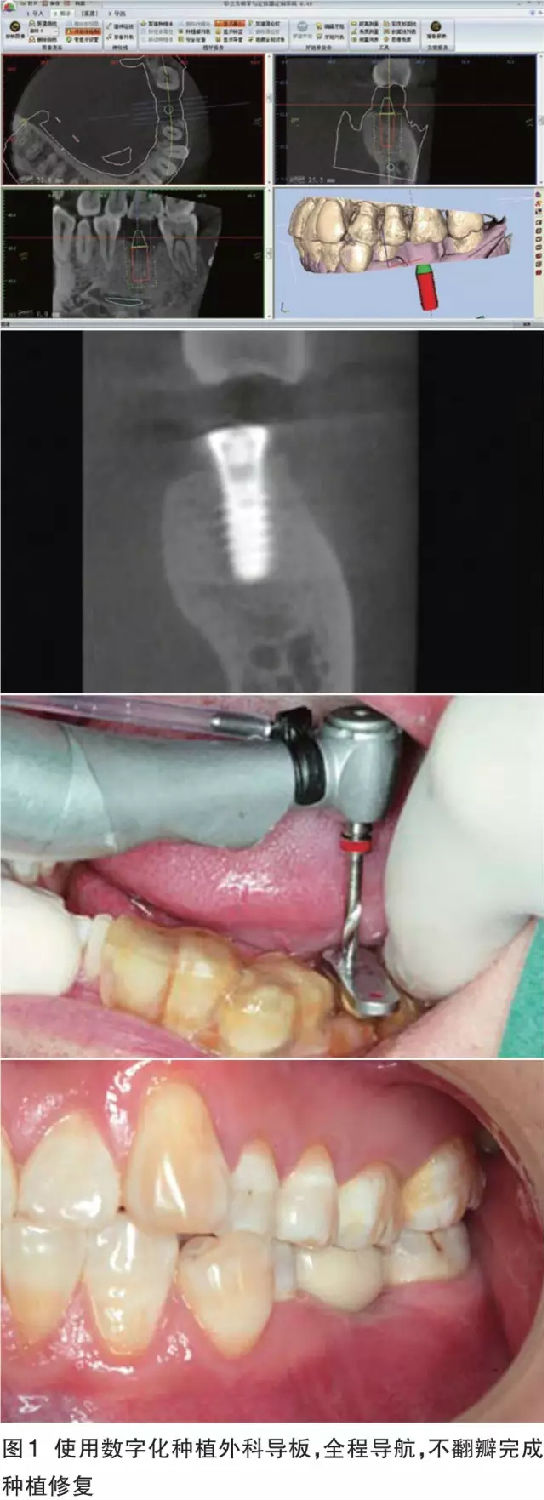

數(shù)字化導(dǎo)板的優(yōu)勢(shì) 對(duì)于軟硬組織充足、解剖條件好,導(dǎo)板能夠容易精準(zhǔn)就位的病例,如果患者經(jīng)濟(jì)條件允許,全套的數(shù)字化解決方案可以預(yù)見性地、完美地、即刻恢復(fù)缺失牙患者的美觀和功能。同時(shí)可以幫助無經(jīng)驗(yàn)的醫(yī)師規(guī)避重要解剖結(jié)構(gòu)、減少外科風(fēng)險(xiǎn)、獲得術(shù)前根據(jù)修復(fù)效果設(shè)計(jì)的最佳種植體位置(圖1)。